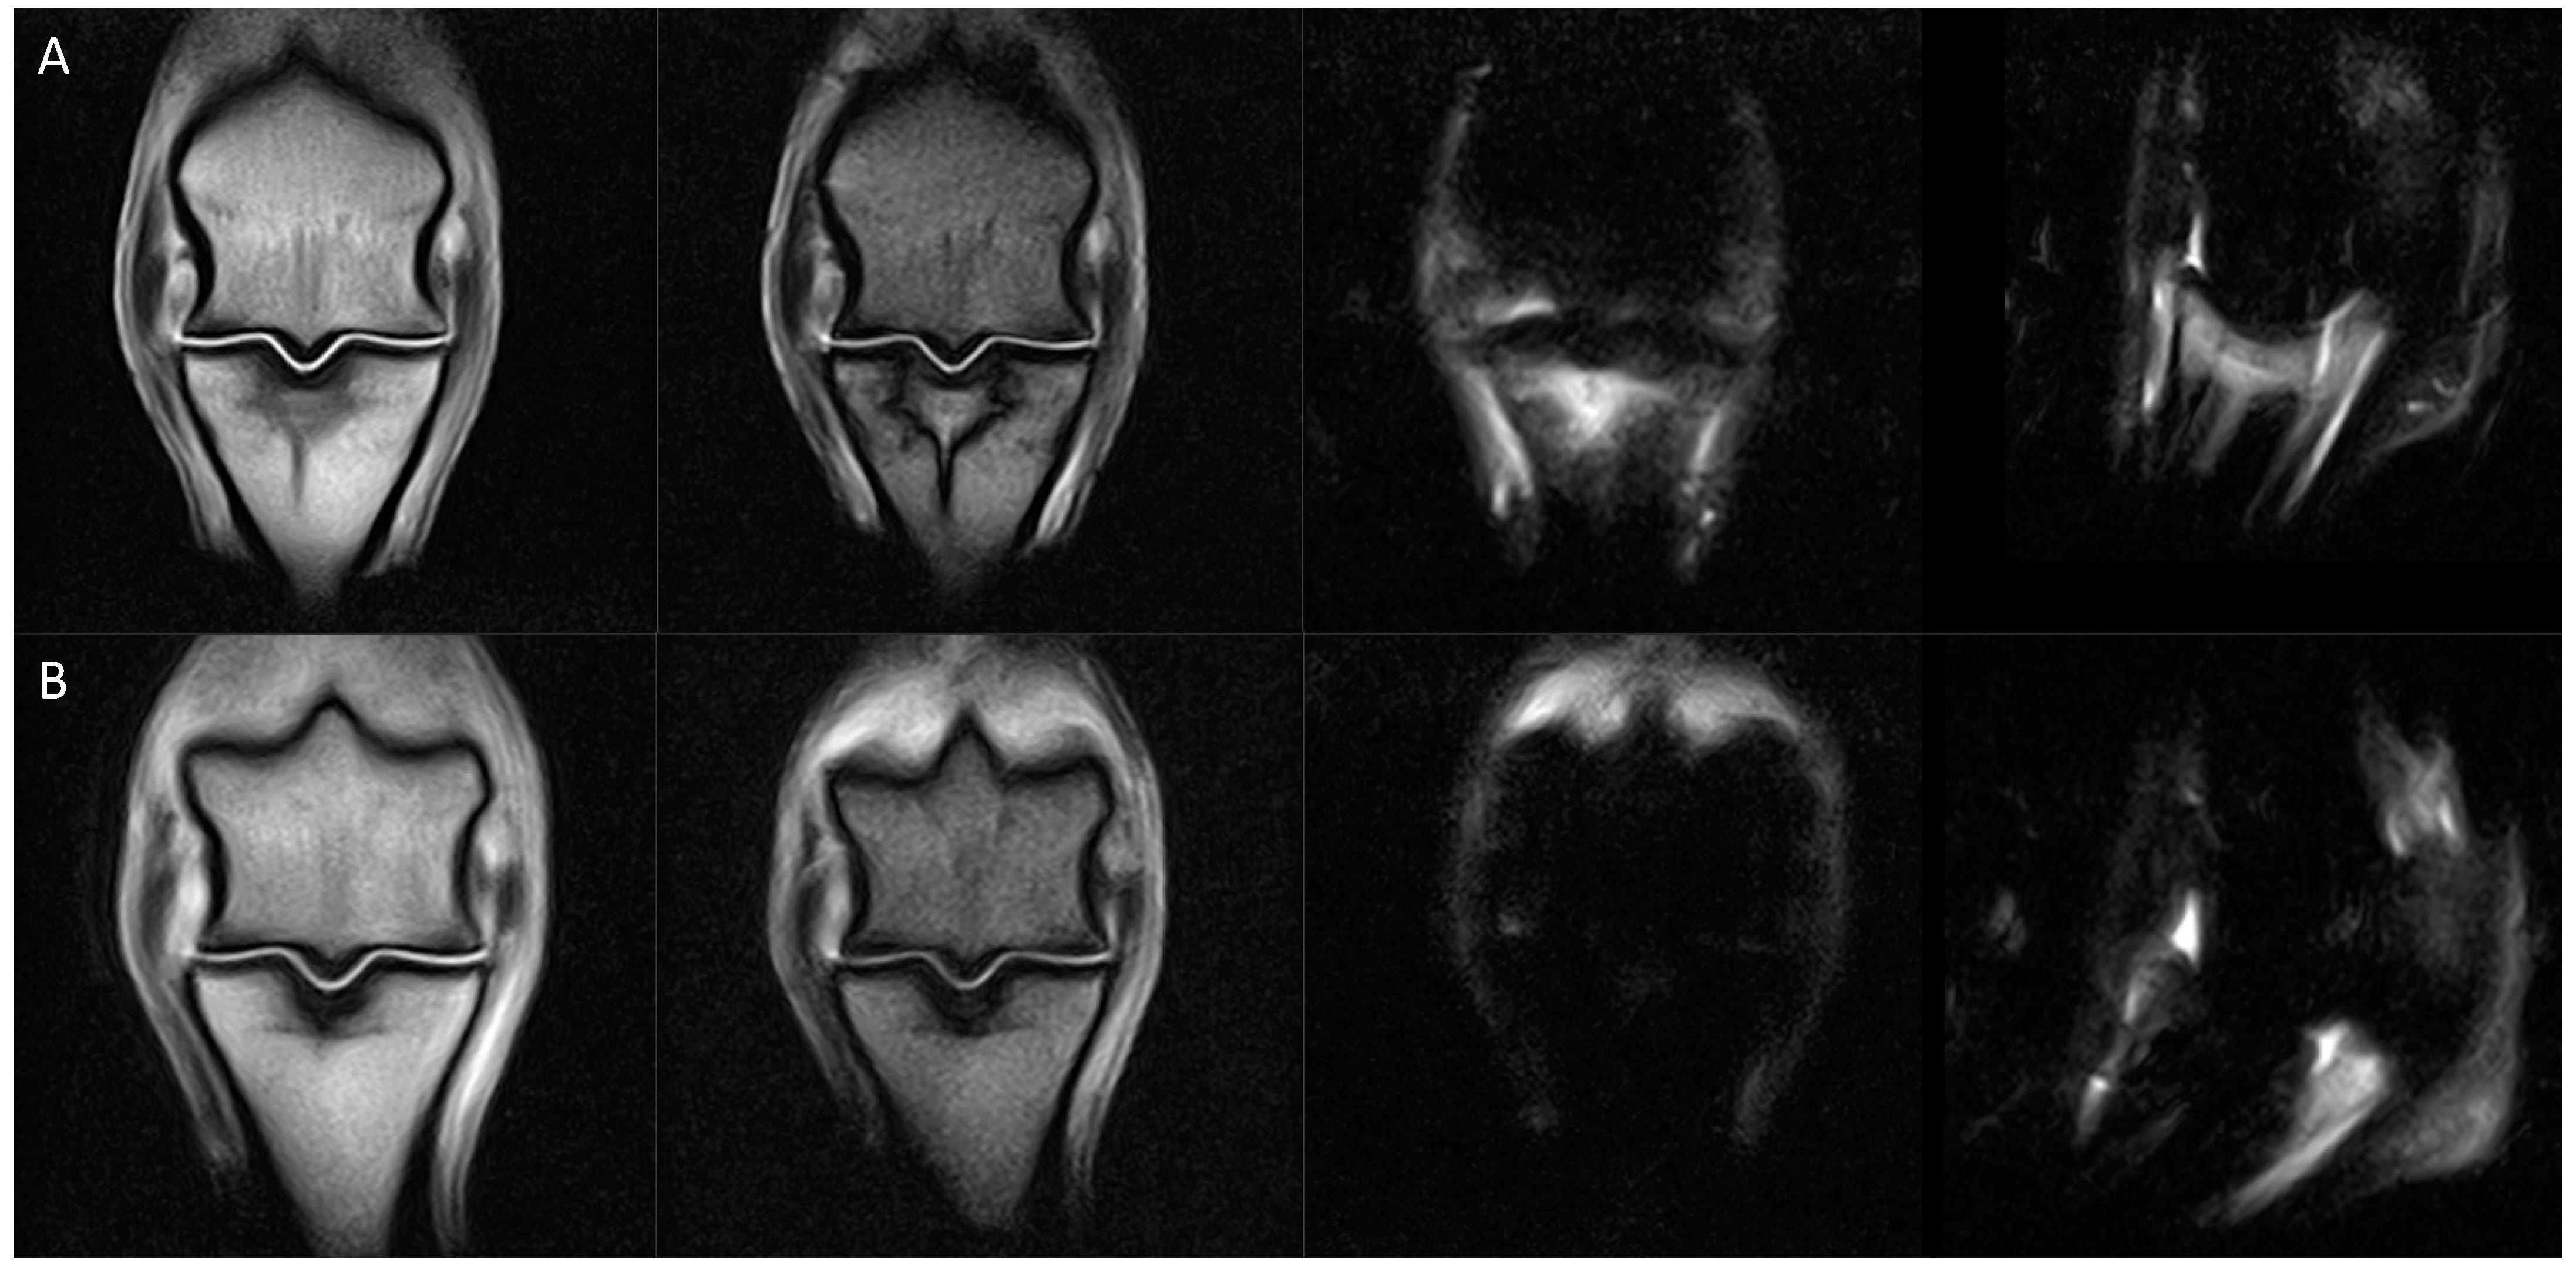

| SGD MRI Classification | Sub-Classifications and Description of Key Osseous Changes in the Sagittal Groove of the Proximal Phalanx | Absent Concurrent Features | Potential Concurrent Features | |

|---|---|---|---|---|

| 0 | Normal | No abnormalities | N/A | N/A |

| 1 | Small subchondral defect | (a) Minor, shallow defect in the chondro-osseous junction (typically ≤1 mm depth ± visible in only one slice) | Demineralisation, osseous densification, bone oedema-like signal | N/A |

| (b) Microfissure (proximodistally oriented, narrow, linear defect in the chondro-osseous junction that is contained within the subchondral bone plate, ≤3 mm length) | ||||

| 2 | Osseous densification | (a) Mild osseous densification of the subchondral ± trabecular bone, not extending to the proximal physis/physeal scar (proximodistal extent less than the equivalent depth of the SG) | Microfissure, demineralisation, bone oedema-like signal | Minor subchondral defect |

| (b) Moderate to severe osseous densification of the subchondral ± trabecular bone, extending to or beyond the proximal physis/physeal scar (proximodistal distance greater than one times the depth of the SG) | ||||

| 3 | Subchondral microfissure with osseous densification | (a) Subchondral microfissure (≤3 mm length) with mild osseous densification (does not reach the proximal physis/physeal scar) | Subchondral demineralisation or bone oedema-like signal | |

| (b) Subchondral microfissure (≤3 mm length) with moderate to severe osseous densification (extending to or beyond the proximal physis/physeal scar) | ||||

| 4 | Bone oedema-like signal within the subchondral ± trabecular bone | (a) Bone oedema-like signal within the subchondral ± trabecular bone | Microfissure, demineralisation | Minor subchondral defect, osseous densification of any extent |

| (b) Bone oedema-like signal within the subchondral ± trabecular bone with microfissure (short proximodistally oriented, narrow, linear defect contained within the subchondral bone plate (≤3 mm)) | Demineralisation | Osseous densification of any extent | ||

| (c) Bone oedema-like signal within the subchondral ± trabecular bone with subchondral demineralisation (unipartite or tripartite regions of demineralisation/resorption within the subchondral bone plate) | Microfissure, osseous densification of any extent | |||

| 5 | Incomplete macrofissure/fracture | Proximodistally oriented linear signal abnormality (>3 mm length; unipartite or tripartite configuration) extending through the subchondral bone and terminating within the trabecular bone | N/A | Demineralisation, osseous densification or bone oedema-like signal of any extent |

| 6 | Complete fracture | Proximodistally oriented linear signal abnormality extending through the subchondral and trabecular bone and exiting at the diaphyseal cortex or distal subchondral bone plate with the creation of two or more fragments | N/A | Demineralisation, osseous densification or bone oedema-like signal of any extent |